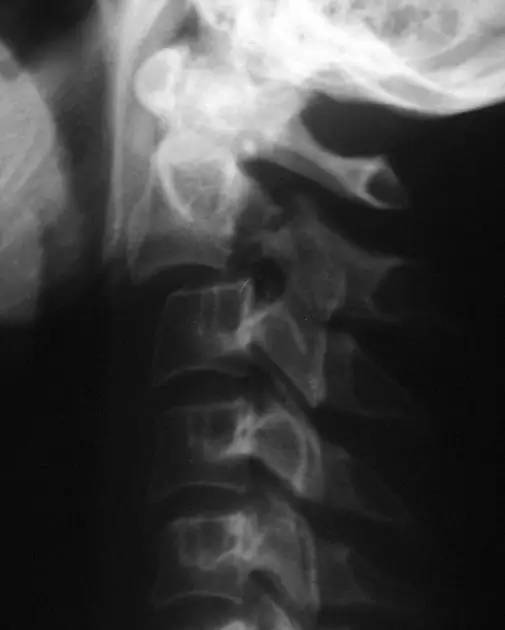

寰椎环的压缩性骨折,骨折是由枢椎压缩性外力引起,骨折多发生在寰椎前侧后侧以及侧方小关节。

第一颈椎双侧性前、后弓骨折,X 线片上很难发现骨折线,有时在正位片上看到 C1 关节突双侧性向外移位,侧位片上看到寰椎前后径增宽及椎前软组织肿胀阴影,CT 检查最为清楚,而 MRI 检查智能显示脊髓损伤情况。

A 图是稳定的 Jefferson 骨折(横韧带完整)轴位像。B 图是不稳定的 Jefferson 骨折(横韧带撕裂)轴位像